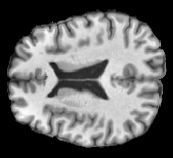

In order to analyze qualitatively the results of our generator, we extract slices with different WMHs loads, Table 4 shows the reconstruction results for three different levels of loads. As we can see in the first row, both methods produce a similar response in regions with a low load of lesions, it can be observed that generated images are similar to the real FLAIR images in the left, and these not present evident structural distortions. However, it can be noted images exhibit blurred effects, which can be due to L2 based optimization, more complex generative networks with adversarial loss optimization as GANs tend to eliminate blurred effect but at the expense to produce structural distortions. In the application presented in this work it is important to preserve the structural information, thus, our L2 based optimization present a good balance between preserve structural information and blurred effects. In the second and third column, it can be observed the performance of both methods when facing the presence of lesions, as can be seen, both methods have a good response to large and contiguous lesions. It also can be noted both methods tend to produce poor performance in small and diffuse WMHs marked in red, note, these lesion do not exhibit identifiable patterns in T1 images, however it can be seen that our proposed method is more sensitive to these patterns which enable to highlight some small regions as those marked in green.

FLAIR T1 Offline synthesis Proposal

[Uncaptioned image] [Uncaptioned image] [Uncaptioned image] [Uncaptioned image]

Table 4: Results of Generation for all the proposed methods,